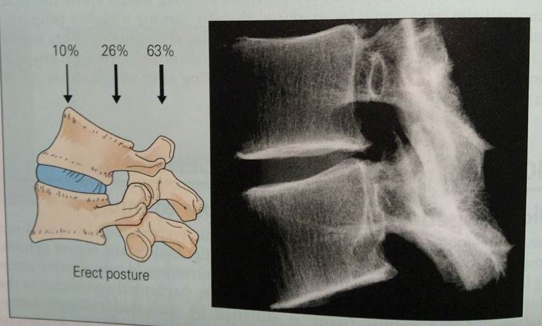

the pain is variable and related to posture/position